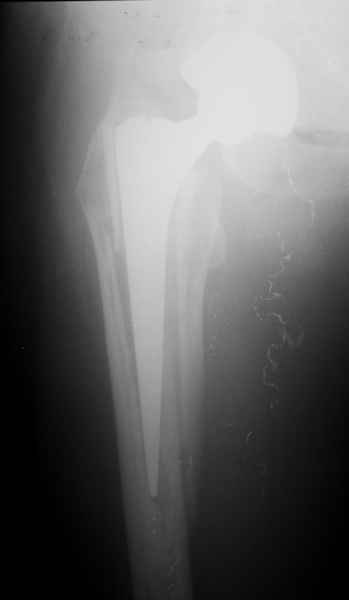

Уважаемые коллеги, продолжая дискуссию, начатую на "Вреденовских чтениях", хочу сказать, что принципиально сущестует два возможных варианта лечения.

1.Остеосинтез на ножке. Мне кажется, что применительно к этому случаю малоперспективный вариант. Синтез хорош, когда можно его выполнить в малоинвазивном исполнении и достигнуть стабильности. Действительно, если ножка б/цементной фиксации после этого не будет иметь фиксации, то ревизия не будет иметь проблем. В представленном случае стабильность синтеза сомнительная, а проведение доп.иммобилизации приведет к контрактуре суставов.

2. Применение ножки дистальной фиксации, мы отдаем предпочтение ножке Вагнера с фиксацией проксимального отдела на ножке. Более травматичное вмешательство, но при стабильной фиксации ножки реабилитация идет в обычном режиме.

Хочется показать два подобных случая, П-ка З. 72 лет и п-т Г. 80 лет. Сразу принимаю замечание, что это были ножки цементной фиксации, просто под руками не было бесцементника.